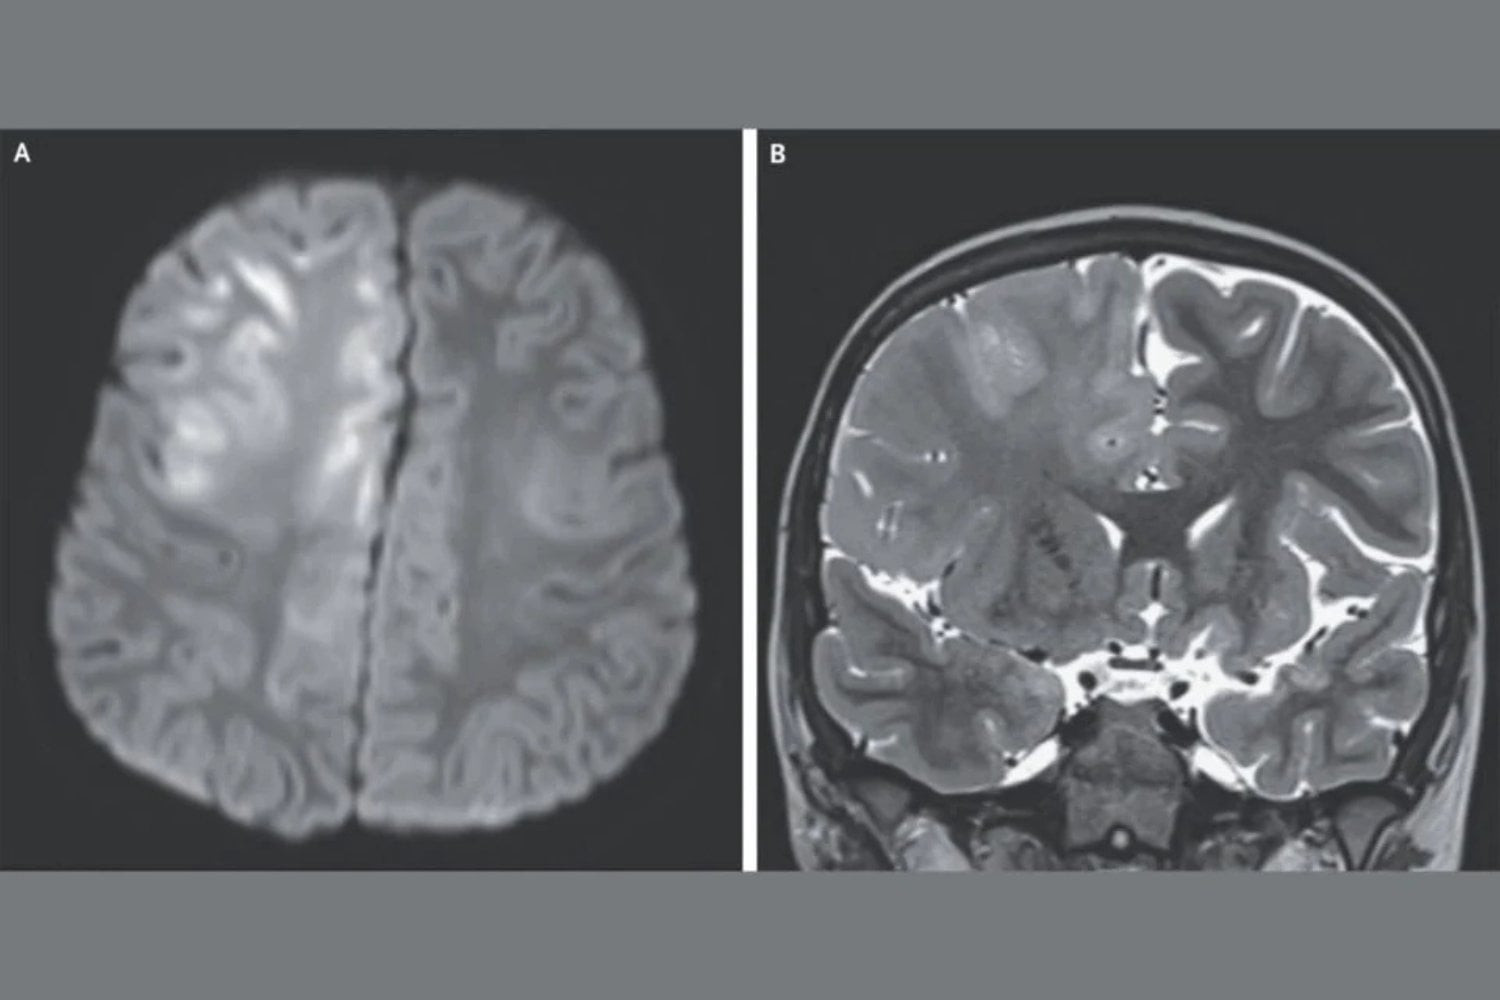

En este caso el niño de 7 años consultó al médico después de tres meses de sufrir convulsiones y deterioro cognitivo. Ya no podía hablar, y en la resonancia magnética (las imágenes que hay arriba) se observó que el cerebro estaba extensamente dañado. El niño había enfermado de sarampión cuando tenía 7 meses y estaba viviendo en Afganistán, donde el virus es endémico. El análisis del líquido obtenido en la punción lumbar reveló altos niveles de anticuerpos contra el virus del sarampión. Eso, aparejado con la historia de haber enfermado de sarampión, más los resultados de un electroencefalograma, hizo que los médicos le diagnosticaran panencefalitis esclerosante subaguda.